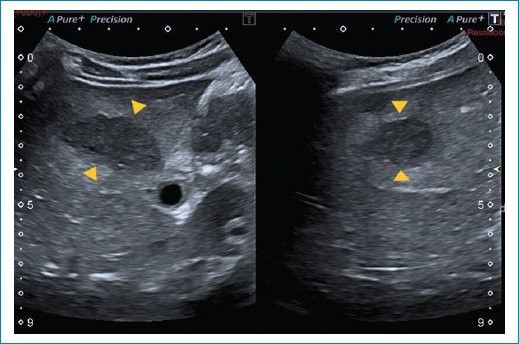

Se trata de una paciente de sexo femenino de 9 años, previamente sana, quien consultó al servicio de guardia pediátrica de nuestra institución por presentar síndrome febril prolongado de 12 días de evolución, sin otro síntoma asociado. A su ingreso, el examen físico reveló buen aspecto general. Se realizó una ecografía abdominal donde se evidenciaron lesiones redondeadas, hipoecoicas, de bordes regulares, que comprometían el parénquima hepático y esplénico (Figs. 1 y 2), las cuales fueron interpretadas como abscesos. Se complementó su estudio con tomografía computada (TC) de abdomen y pelvis con contraste endovenoso, siendo el hallazgo principal la presencia de múltiples imágenes hipodensas con morfología en racimos y realce en anillo tras la administración del contraste endovenoso, distribuidas en el parénquima hepático y esplénico, destacándose la mayor de 29 mm en segmento V hepático (Figs. 3 y 4). Debido a los hallazgos por imágenes y el estado clínico de la paciente, el primer diagnóstico que se planteó fue el de EAG. Se consideraron las lesiones hipodensas múltiples del hígado y bazo como una manifestación importante de enfermedad diseminada o atípica3,5,6. La madre confirmó un gato como mascota, lo cual estaba a favor de nuestra impresión diagnóstica.

Para realizar el diagnóstico de EAG se utilizan pruebas serológicas que detectan la presencia de anticuerpos contra B. henselae4,8. A nuestra paciente se le realizaron pruebas de anticuerpos B. henselae IGG e IGM cuyo resultado fue positivo (1/1.280). Los estudios de imágenes poco aportan ante cuadros de EAG típico, podemos encontrar en la evaluación ecográfica ganglios linfáticos aumentados de tamaño con pérdida de su ecoestructura habitual, generalmente con necrosis central y asociados a edema circundante. Sin embargo, en pacientes con enfermedad atípica o diseminada se han asociado hallazgos característicos que pueden ser útiles para establecer el diagnóstico como la formación de múltiples granulomas hepáticos y esplénicos, con o sin hepatoesplenomegalia, identificados mediante ecografía y TC3. Estos granulomas se identifican inicialmente como lesiones hipoecoicas en ecografía, y en algunos casos presencia de calcificaciones en las fases tardías. En TC presentan características similares a cualquier absceso, hipodensos, redondeados o con morfología en racimos y tras la administración del contraste pueden permanecer hipodensos o mostrar un realce periférico característico. La multiplicidad y el compromiso de varios órganos se relacionan más con infecciones bacterianas, a diferencia de las de origen parasitario, lo cual nos orienta a un mejor diagnóstico.